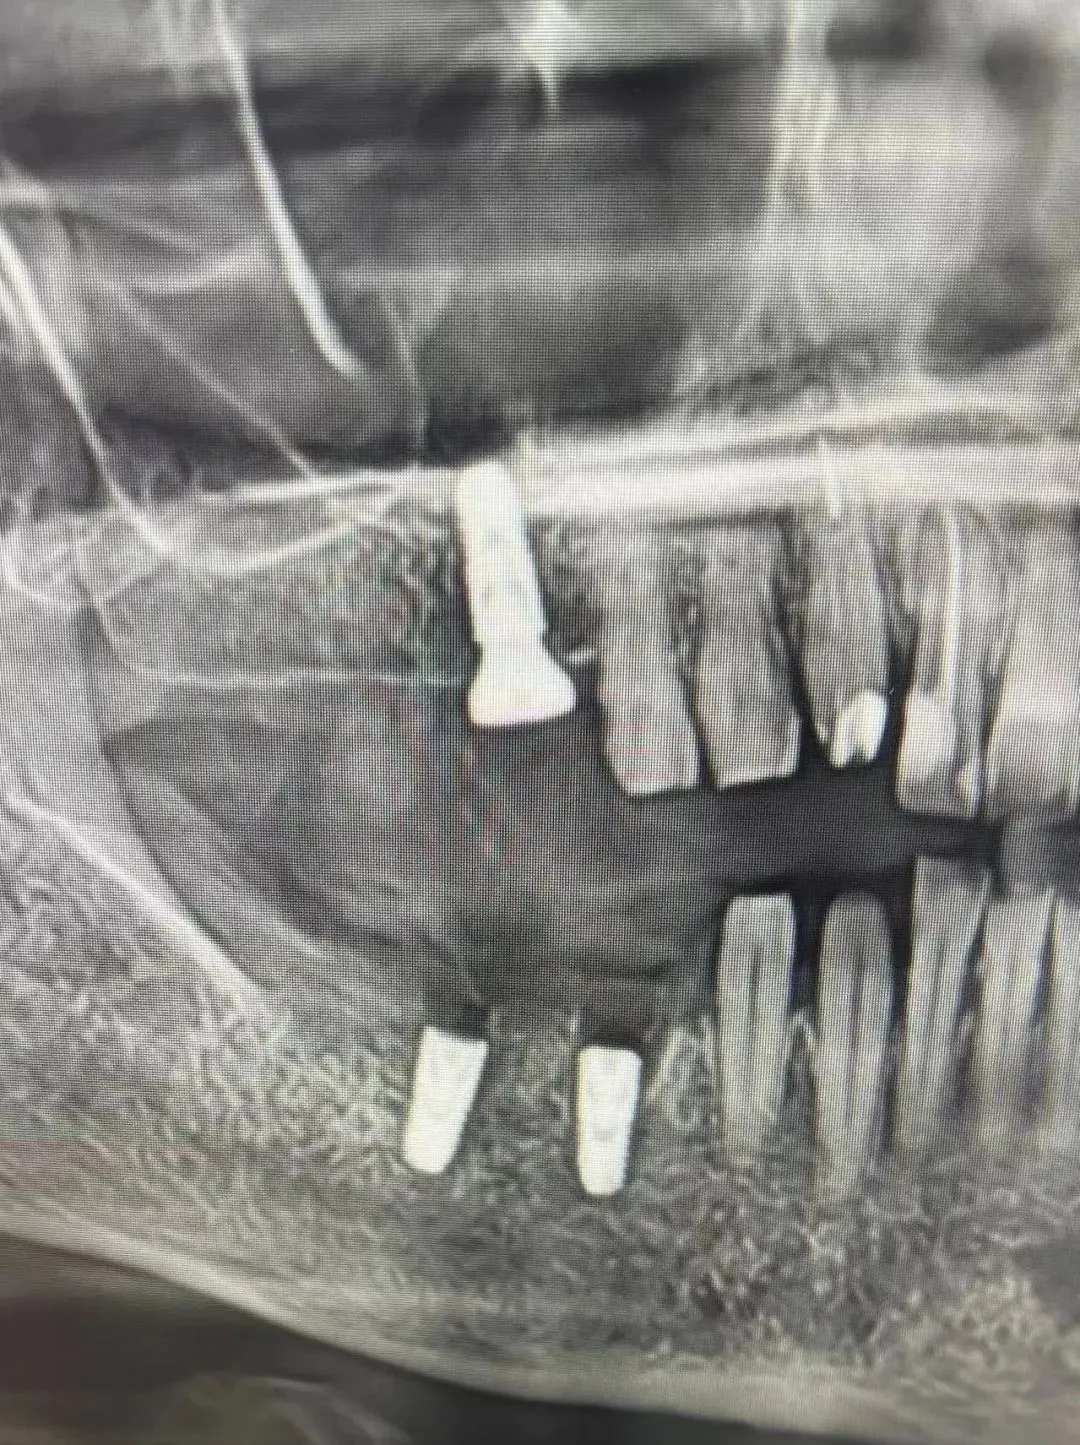

7、种植影像学分析;可以获得骨高度 ,骨宽度信息 ,甚至可以模拟种植体植入位点

六、学员回家后部分病例